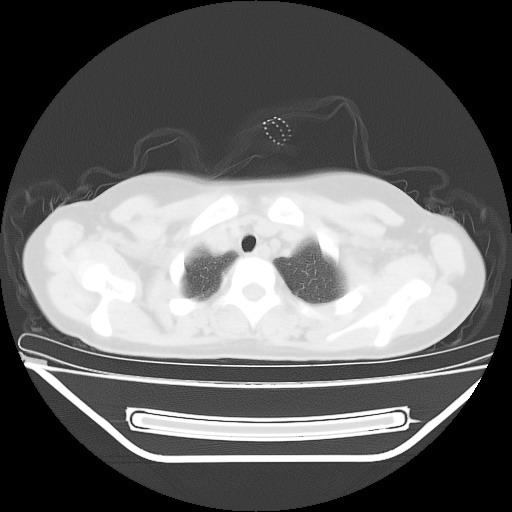

女,12岁,前期发热,咳嗽,无痰,经头孢抗炎无效。ct右肺上叶实变影.5天后公布病理结果。以下是2010-2-13ct片

胸腺瘤待排

从发病部位考虑胸腺瘤可能。

肺内病变,炎症?异物?

从发病部位考虑胸腺瘤可能。

考虑内胚窦瘤可能性大。

定位肺外,年龄小,还是先考虑畸胎瘤,左上肺膨胀不全并炎症。

鉴别:内胚窦瘤恶性程度高,有胸水;淋巴瘤、胸腺瘤、sftp等年龄大;异物上叶少见,无肺气肿及纵膈偏移不支持;炎症定位不考虑肺内所以排除。

考虑畸胎瘤破溃并左肺上叶炎症。

来源于胸腺的病变.

左前上纵膈可见大块影,与大血管关系密切,邻近肺少许炎症,考虑左前上纵膈占位,胸腺瘤或畸胎瘤,并左上肺膨胀不全。